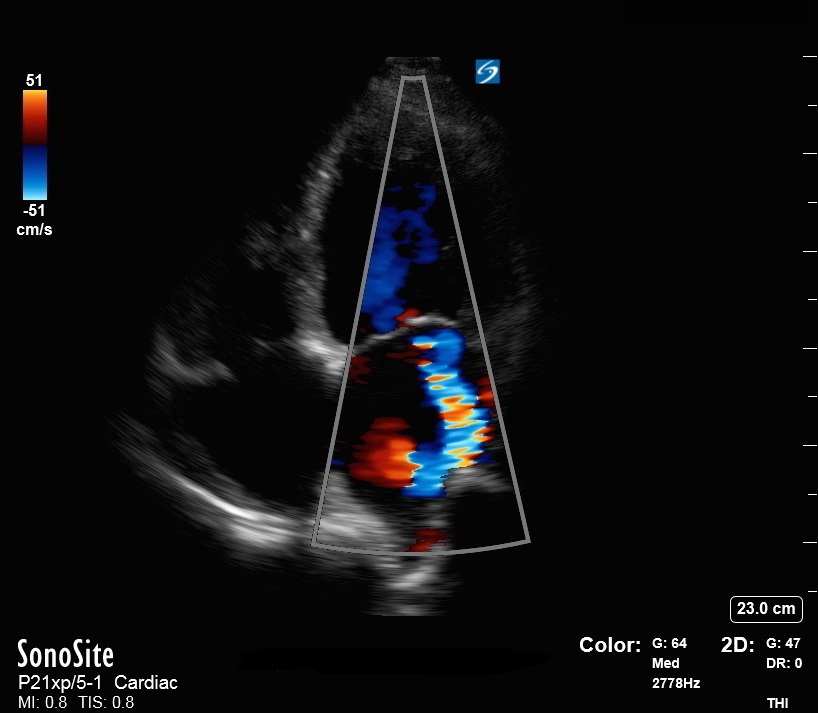

显示二尖瓣反流的心尖 4 腔视图彩色图像